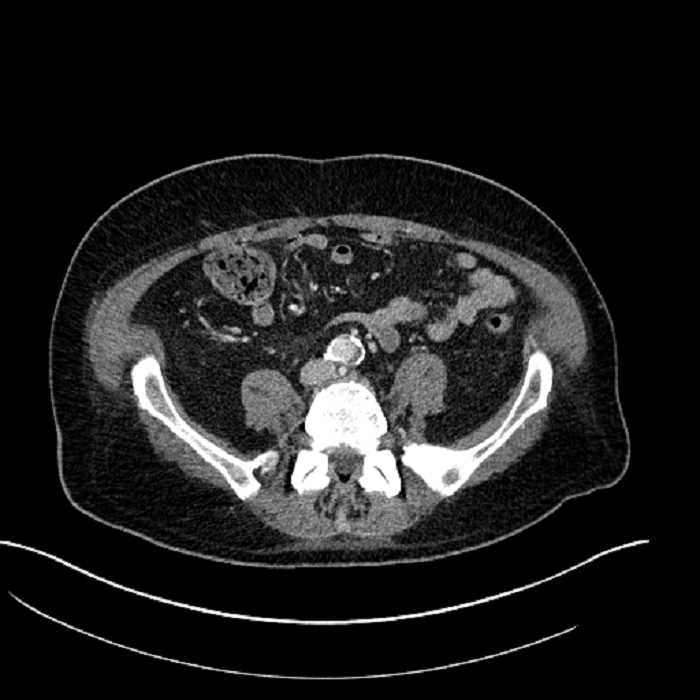

• Large fluid density structure in hepatic segments 7 and 8 measuring 10 x 7 x 7 cm with internal septation and circumferential ill-defined low density compatible with edema

• Peripherally enhancing subcapsular collections along the anterior margin of the left hepatic lobe measuring 3 x 1 cm and 2 x 1 cm

• Mild mural thickening of a segment of the sigmoid colon with adjacent fat stranding and a 1.5 cm fluid and gas collection along the tip of an inflamed diverticulum

• Loss of the normal fat plane between this collection and adjacent loops of small bowel, which demonstrate mural thickening

• High grade stenosis of the left common iliac artery, with the left internal and external iliac arteries remaining patent

Acute sigmoid diverticulitis complicated by a small contained perforation and a large abscess in the right hepatic lobe. Additional small subcapsular abscesses along the anterior margin of the left hepatic lobe.

Additionally, loss of the normal fat plane between the peridiverticular collection and adjacent thickened loops of small bowel raises the potential for an enterocolonic fistula.

High grade stenosis of the left common iliac artery. The left external and internal iliac arteries are patent.

• The classic CT imaging appearance is a double target sign with internal low density surrounded by an internal enhancing rim (capsule) and a low density external rim (edema)

Hepatic abscess showing the double target sign with low density internally surrounded by a thin inner enhancing rim (red arrow) and ill-defined outer low density rim (yellow arrow). Blue arrow indicates an internal septation. Red arrows: additional smaller subcapsular abscesses. Red arrow: focal contained perforation associated with diverticulitis.